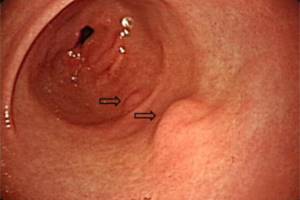

ГЭРБ – хроническое рецидивирующее заболевание, проявляющееся характерными симптомами и/или воспалением дистальных отделов пищевода вследствие рефлюкса – регулярно повторяющегося заброса в пищевод желудочного или дуоденального содержимого. Встречается у.

Гастроэзофагеальная рефлюксная болезнь чрезвычайно распространена и охватывает около 40% среди взрослого населения развитых стран. В странах Восточной Европы этот показатель достигает 40-60%, причем у 45-80% пациентов с ГЭРБ обнаруживается эзофагит

Желчный рефлюкс – синдром, довольно часто сопровождающий такие распространенные заболевания верхних отделов пищеварительного канала, как функциональные диспепсии, гастроэзофагеальную рефлюксную болезнь (ГЭРБ), хронические гастриты...